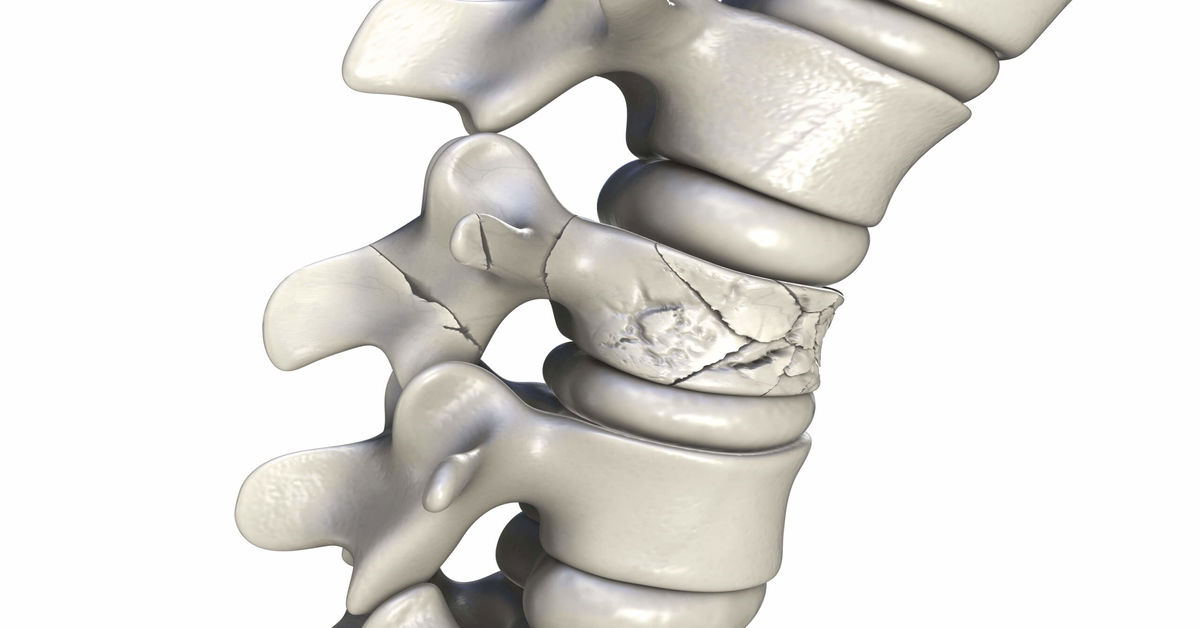

Omur adı verilen omurga kemiklerinin çatlaması veya kırılmasıdır. Bu durum, kazalar, düşmeler veya kemik hastalıkları sonucu oluşabilir. Omurga kırığı, genellikle sırt veya boyun bölgesinde ağrıya neden olur. Bazı durumlarda sinir hasarı olabilir ve felç gibi ciddi sonuçlar doğurabilir. Tedavi, kırığın yerine ve şiddetine bağlı olarak cerrahi müdahale veya korse ile yapılabilir.

Kırığın en yaygın sebeplerinden biri yüksekten düşmeler veya trafik kazalarıdır. Özellikle araba kazaları, bisiklet kazaları ya da düşme sonucu omurgada hasar meydana gelir. Bu tür durumlar, omurgadaki vertebralara yüksek şiddetli darbeler uygulayarak kırılmasına yol açabilir. Osteoporoz, kemiklerin zayıflaması ve kırılgan hale gelmesi durumudur. Özellikle yaşlı bireylerde daha yaygındır.

Osteoporoz, omurga kırığı vakalarını tetikleyen en önemli sağlık sorunudur çünkü kemikler daha kırılgan hale gelir. Bu da basit bir düşme ya da ani bir hareketle bile kırılmalara yol açabilir. Fiziksel travmalar, kırıklara neden olabilir. Bunlar, spor yaparken yaşanan sakatlanmalar, sporculara uygulanan aşırı baskılar veya şiddetli darbeler sonucu oluşabilir. Özellikle temas sporlarında omurga travmalarına sıkça rastlanır.